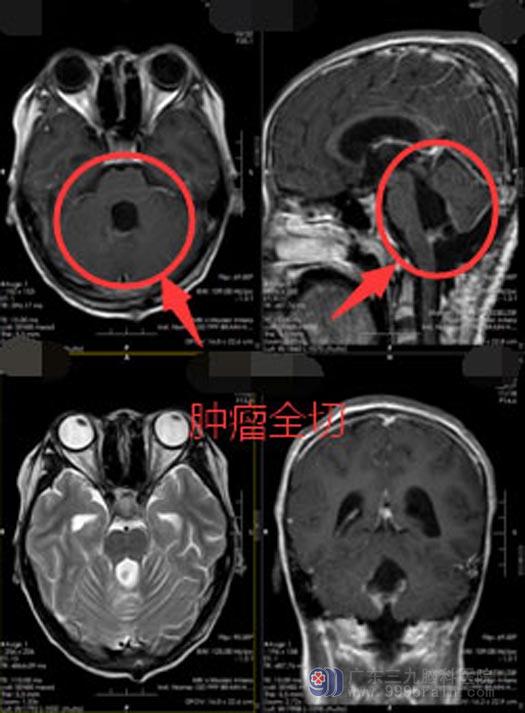

但肿瘤太大,而且是位于脑部功能区,贸然手术不仅手术难度极大,而且小莹的身体状态也承受不了如此大的手术。鲁明副院长带领神经外五科的治疗团队针对小莹的病情迅速制定了治疗方案,先进行外引流,将脑积水这个燃眉之急解决之后,再辅助进行术前放化疗,最后进行手术切除肿瘤。这样既可以减少肿瘤实质细胞,使肿瘤病灶缩小,又可以为手术创造更良好的环境。

很快,小莹接受了脑室外引流术;术后,颅高压的症状立刻得到了改善,她不再频繁的头痛、呕吐,身体状况也慢慢地得到了改善。随即接受了术前放化疗。结束放化疗后,按照之前制定的计划对小荧实施了第二次手术,手术很顺利,将肿瘤全部切除,术后小荧没有出现明显的并发症,术后影像检查未显示肿瘤残留。